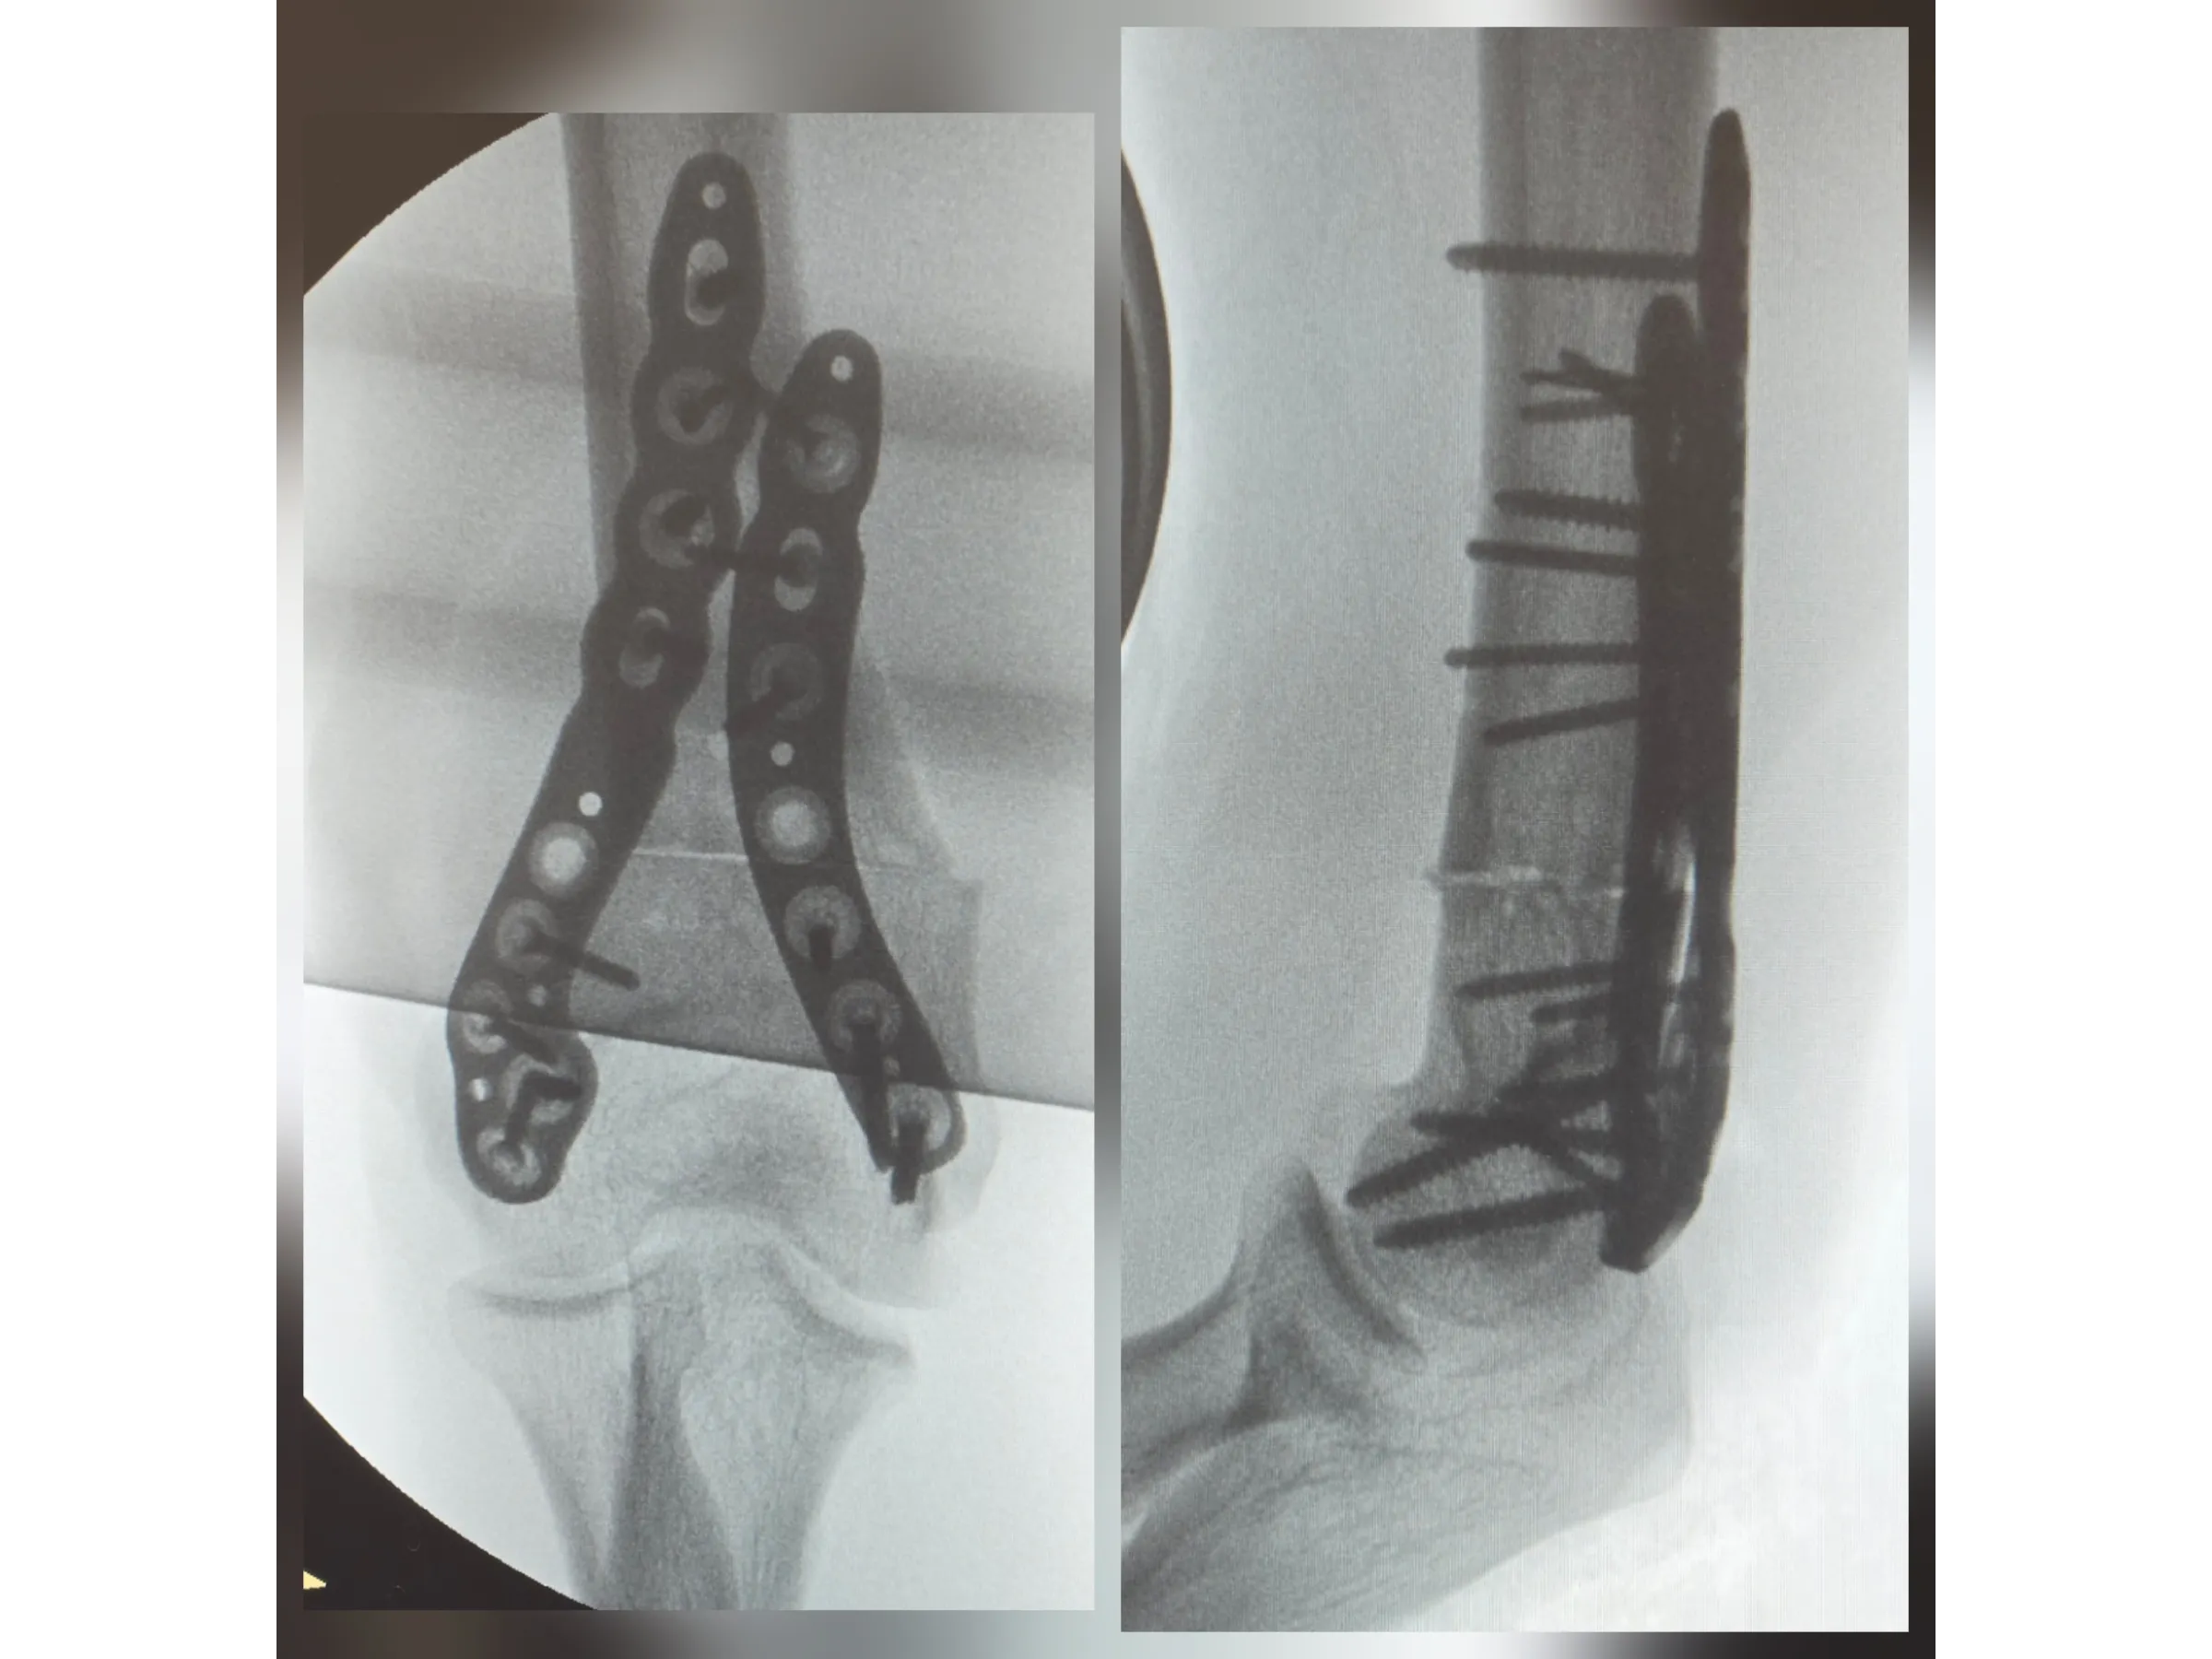

- Osteotomia guiada e fixação com placas bloqueadas;

- Avaliação pós-operatória com foco em estabilidade e alinhamento.

- Fixação Bloqueada Estável: sequência sistemática de placas e parafusos para máxima segurança;

- Avaliação Pós-operatória Objetiva: correção eficaz com mínima morbidade.